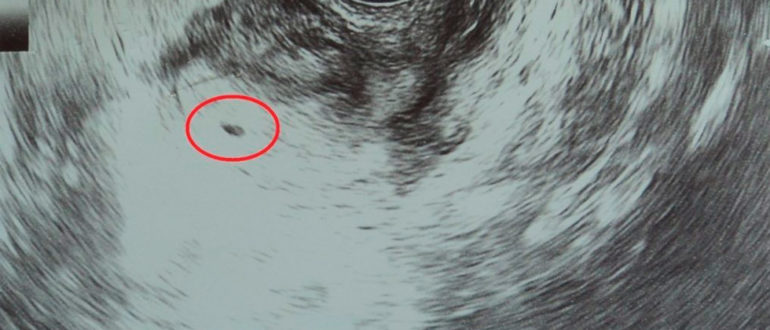

Узи после зачатия

Показывает ли беременность на ранних сроках до задержки на УЗИ: диагностика, расшифровка, определение на первых неделях Желание поскорей узнать о беременности, заставляет женщин обращаться к специалистам ультразвуковой диагностики,…